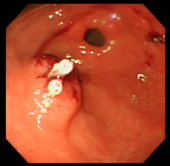

| ポリープ | 根元に生理食塩水を注入して水ぶくれ状態をつくり、膨らんだその部分に スネアをかけて高周波の電流を流し病変部を焼き切っている状態。 |